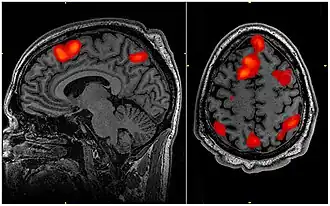

People with ADHD usually accompany with some difficulties on their working memory, when we focus on the brain structure of the ADHD children, we could see that their brain structures are usually differ from children without ADHD, Several brain regions and structures, such as pre-frontal cortex, striatum, basal ganglia, and cerebellum tend to be smaller than people without ADHD. The overall brain size from ADHD children is generally 5% smaller than children without ADHD (Figure 5).These brain regions are closely related to how our working memory works, especially the pre-frontal cortex[83], thus with a smaller brain size, ADHD children’s working memory would perform poorly.